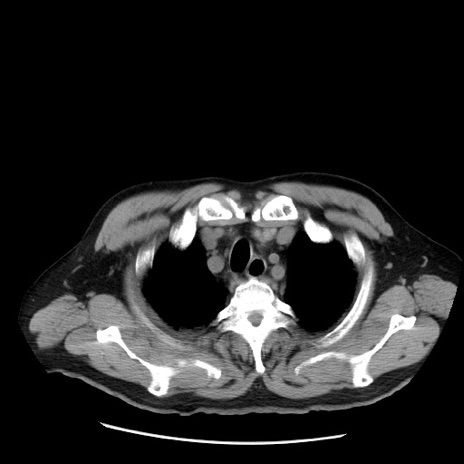

症例20(横断像)

【症例】 60歳代男性

【主訴】 腹部膨満、嘔吐

【現病歴】5日前頃より倦怠感を認め食事量減少し4日前の朝嘔吐、食事摂取困難となった。 3日前近医受診し点滴施行され整腸剤などを処方された。 当日他院を受診し、腹部膨満著明、炎症反応の上昇(CRP10.8、WBC11200)あり、紹介受診となる。

【身体所見】 意識JCS1 受け答えがはっきりしないBP 111/57mHg、 P 67bpm、、BT35.2°C、SpO2 97%(RA)、 腹部:膨隆、打診で鼓音あり、全体的に圧痛有り、腸蠕動音(-)、反跳痛ははっきりせず。

【データ】WBC 11400、CRP 14.20